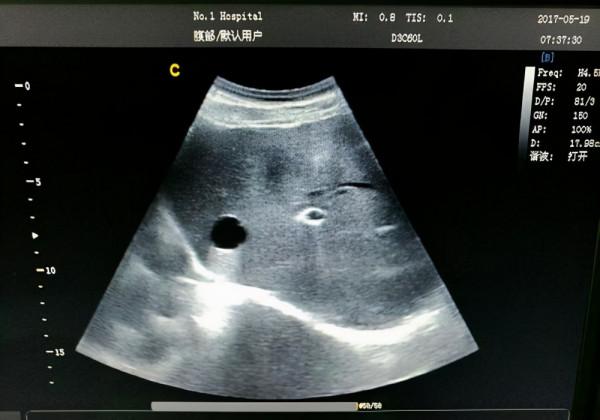

2、肝囊腫

肝囊腫是比較常見的肝臟疾病,很多人在聽到囊腫時會認為是可怕的腫瘤,都認為要治療或者進行手術切除,卻不知有些肝囊腫不需要理會,只需要定期檢查即可。

但如果發現肝囊腫直徑超過5釐米或者有明顯症狀,如腹痛、上腹不適等,就需要及時採取相對應治療措施。在目前肝囊腫最佳治療方法是進行手術治療,不僅安全,創傷性也比較小。